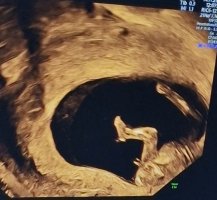

Tror jeg ville tippa gutt jeg! Synes nuben (om det er den vi ser) peker noe oppover sammenlignet med ryggen. Men vanskelig å siKan dere se noe her?

Jeg ser for meg det er jente![]()

Fikk «slightly leaning boy» fra admin på fb gruppe. Må jo være nuben vi ser daTror jeg ville tippa gutt jeg! Synes nuben (om det er den vi ser) peker noe oppover sammenlignet med ryggen. Men vanskelig å si![]()

Ja, det er nok det da! SpennendeFikk «slightly leaning boy» fra admin på fb gruppe. Må jo være nuben vi ser da![]()